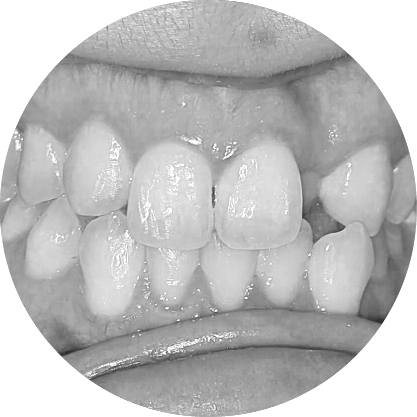

ตัวอย่างในชีวิตจริง

Crowded teeth model – overlapping or twisted teeth

ฟันซ้อน (Overcrowded Teeth)

Creating Space for Crowded Teeth

ฟันเกคือภาวะที่ขากรรไกรมีพื้นที่ไม่เพียงพอ ทำให้ฟันซ้อนหรือเรียงตัวไม่เป็นระเบียบ การรักษาช่วยเพิ่มพื้นที่เพื่อจัดฟันให้เข้าที่อย่างเหมาะสม ส่งผลให้รอยยิ้มดูสวยงามขึ้นและสุขภาพช่องปากดีขึ้นด้วย